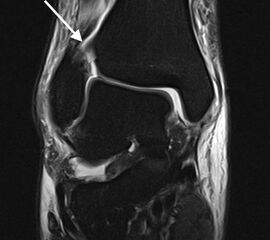

Magnetresonanztomographie (MRT)

Die Magnetresonanztomographie stellt aktuell den Goldstandard in der Diagnostik von Syndesmosenverletzungen dar (Szeimies 2013). Beschrieben sind eine Sensitivität von 100% und eine Spezifität von 93% bei Verletzungen des AITFL, sowie eine Sensitivität und Spezifität von 100% bei Verletzungen des PITFL. Darüber hinaus ermöglicht das MRT weitere ligamentäre, chondrale oder intraossäre Verletzungen zu detektieren. Bei chronischen Syndesmosenverletzungen sollte eine MRT-Diagnostik mit Kontrastmittel (KM) intravenös durchgeführt werden, da diese eine höhere Spezifität und Sensitivität im Vergleich zur nativen MRT-Bildgebung aufweist. Durch die zusätzliche Gabe von KM können durch eine Mehranreicherung des KM im Bereich der Syndesmose Rückschlüsse auf das Vorhandensein einer chronische Instabilität gezogen werden 41.

ANMERKUNG:

Trotz der höheren Sensitivität und Spezifität der MRT Diagnostik im Vergleich zum konventionellen Röntgen, handelt es sich bei beiden Techniken um statische Untersuchungen. Entsprechend geben diese keinen Rückschluss auf eine mögliche dynamische Instabilität.